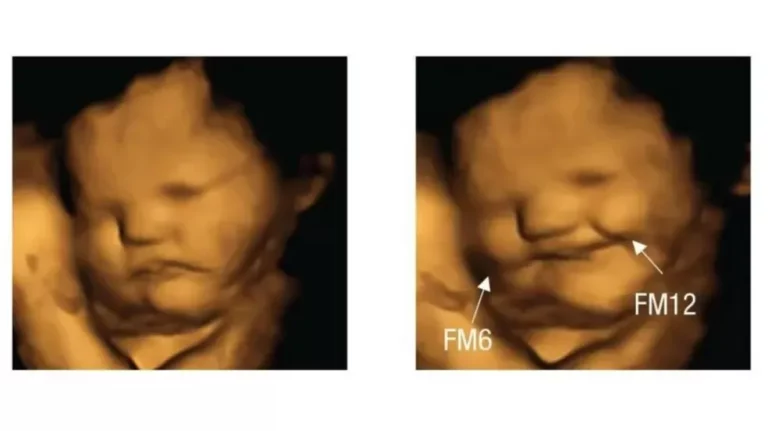

Bebês no útero sorriem para cenouras e fazem careta para couve

Se comer couve provoca uma careta em você, saiba que você não está sozinho. Uma pesquisa científica descobriu...